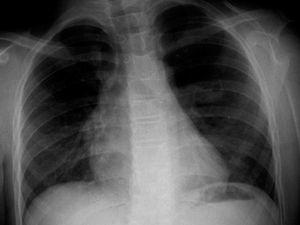

Figura 1. Radiografía de tórax en la que se aprecia una imagen cavitada en la región parahiliar izquierda. No se visualiza atrapamiento aéreo.

Los hallazgos radiológicos pueden mostrar una masa hiliar en el 89 % de los casos (6), un área de hiperlucidez pulmonar en el 67 %6 o una asociación de ambos en el 67 %6. La hiperlucidez es el resultado de la asociación de la oligohemia y un incremento del volumen de aire en el parénquima afectado. La acumulación de secreciones y su enclavamiento en el extremo distal de la atresia determina la aparición de opacidades ovaladas, redondas o ramificadas cerca del hilio, constituyendo el mucocele. Es posible diagnosticar la atresia bronquial congénita con sólo una radiografía de tórax (6). En el caso que se presenta, en la radiografía (fig. 1) sólo se percibe una imagen cavitada parahiliar sugerente de broncocele, sin área de hiperlucidez asociada.